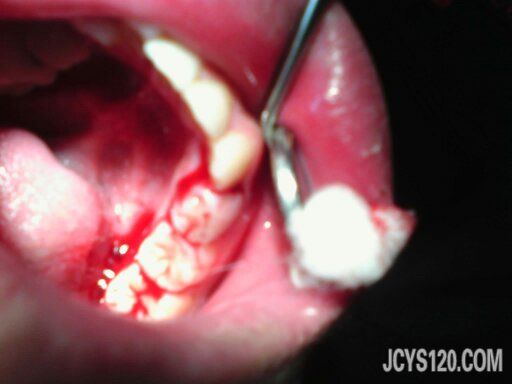

检查:体温、脉搏、心率、呼吸正常,心肺(-)腹部(—),膝关节无畸形。口腔检查见右侧下颌第四乳磨牙2度松动,舌侧见一活动性的出血点,无血块形成。

处理:局部用止血海绵填塞压迫止血,考虑患者使用常规止血药无效,所以没有点滴止血药。其他的如图:

第二张图片表明出血已经停止。观察10分后离开。